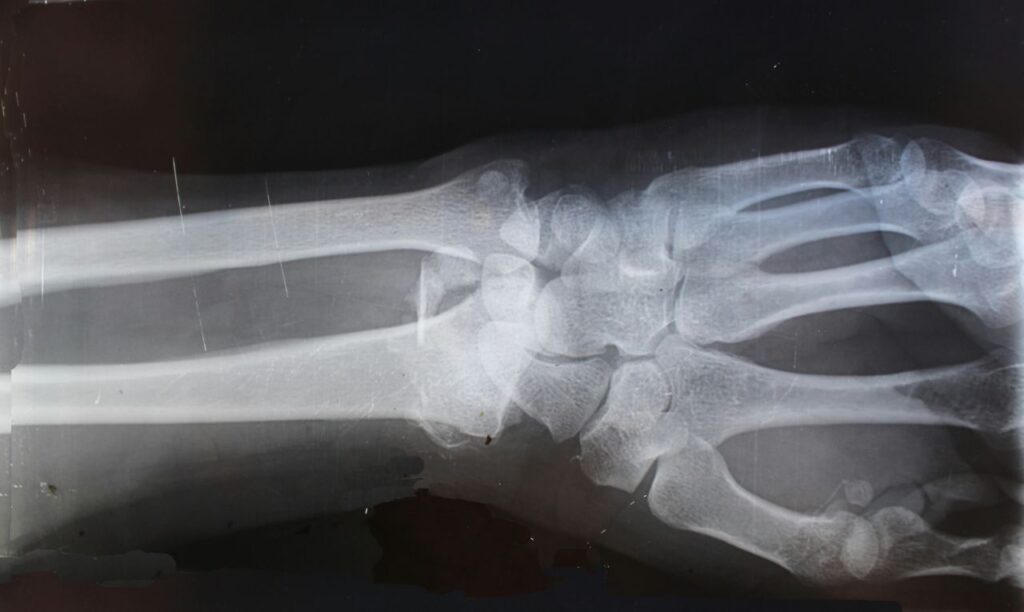

In uno dei casi clinici, un giovane lavoratore con una frattura complicata del polso è stato operato in soli tre minuti attraverso un’incisione di 2-3 centimetri. Con il metodo tradizionale sarebbe servita un’incisione molto più grande per impiantare placche e viti, con rischi di danni ai tendini e ai nervi. Il paziente ha recuperato completamente in tre mesi senza complicazioni.

I test clinici hanno coinvolto oltre 150 pazienti in diversi ospedali cinesi, mostrando risultati promettenti. Bone 02 si rivela particolarmente utile per le fratture comminute, quando l’osso si spezza in tre o più frammenti, situazioni dove i metodi tradizionali risultano complicati da applicare.